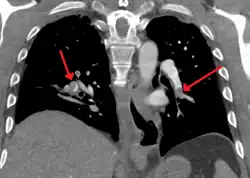

CT pulmonary angiography

CT pulmonary angiography (CTPA) is a pulmonary angiogram obtained using computed tomography (CT) with radiocontrast rather than right heart catheterization. Its advantages are that it is accurate, it is non-invasive, it is more often available, and it may identify other lung disorders in case there is no pulmonary embolism. The accuracy and non-invasive nature of CTPA also make it advantageous for people who are pregnant.[61]

On CT scan, pulmonary emboli can be classified according to the level along the arterial tree. -

Segmental and subsegmental pulmonary emboli on both sides -

CT pulmonary angiography showing a "saddle embolus" at the bifurcation of the main pulmonary artery and thrombus burden in the lobar arteries on both sides

Assessing the accuracy of CT pulmonary angiography is hindered by the rapid changes in the number of rows of detectors available in multidetector CT (MDCT) machines.[62] According to a cohort study, single-slice spiral CT may help diagnose detection among people with suspected pulmonary embolism.[63] In this study, the sensitivity was 69% and specificity was 84%. In this study which had a prevalence of detection was 32%, the positive predictive value of 67.0% and negative predictive value of 85.2%. However, this study's results may be biased due to possible incorporation bias, since the CT scan was the final diagnostic tool in people with pulmonary embolism. The authors noted that a negative single-slice CT scan is insufficient to rule out pulmonary embolism on its own. A separate study with a mixture of 4-slice and 16-slice scanners reported a sensitivity of 83% and a specificity of 96%, which means that it is a good test for ruling out a pulmonary embolism if it is not seen on imaging and that it is very good at confirming a pulmonary embolism is present if it is seen. This study noted that additional testing is necessary when the clinical probability is inconsistent with the imaging results.[64] CTPA is non-inferior to VQ scanning, and identifies more emboli (without necessarily improving the outcome) compared to VQ scanning.[65]